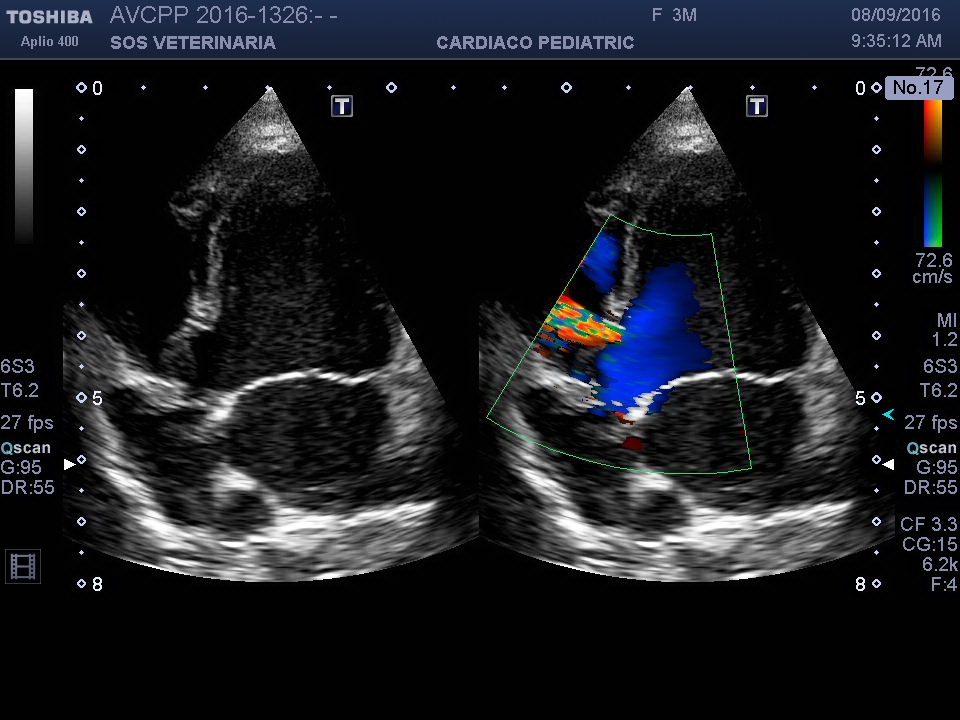

Cucciolo di setter maschio eta’ 3 mesi ,ricoverato per gastroeneterite virale positivo alla parvovirosi ,severa diarrea emorragica ,trattamento intensivo :cristalloidi ,plasmaexspander ,plasma ,stimolatori del midollo (myelostim) ,il soggetto ha superato la fase acuta e ha ripreso ad alimentarsi dopo 5 gg . Presente alla visita un soffio sistolico ,eseguito l’ecocardiogramma durante il decorso che ha evidenziato un DIV perimembranoso di piccole dimensioni a pattern restrittivo e scompenso sistolico .

Visualizzando i filmati e’ evidente l’insufficienza contrattile e sovraccarico volumetrico e il DIV con il pattern restrittivo